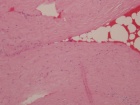

62 year old male began having trouble with his left wrist and forearm after shoveling snow 5 months prior to evaluation. Pain is improving.

Zoom image: Cell stain Cell stain.